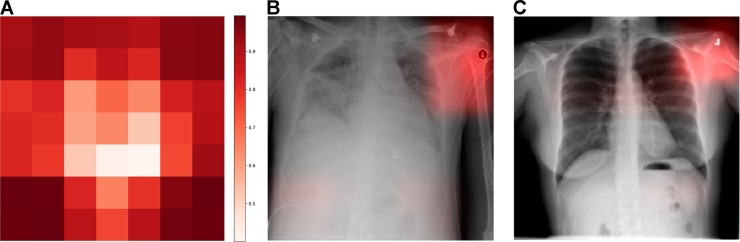

Explainability¶

Deep learning modellen zijn alomtegenwoordig voor computer vision taken. Dit type modellen zijn echter in grote mate black boxes. Het is heel moeilijk om model parameters te interpreteren en bijgevolg om te begrijpen hoe een specifieke modeloutput tot stand komt. Hierdoor ontstaat ook een ernstig risico op model artefacten.

Interpreteerbaarheid: Complexe, ontransparante modelarchitectuur - weliswaar zijn technieken ontwikkeld om inzicht te krijgen in feature maps